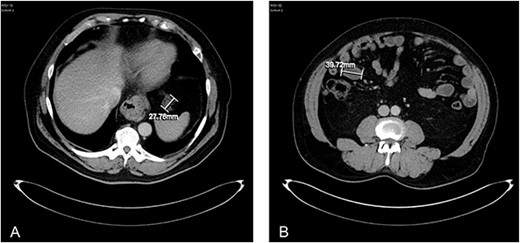

About 1 year later, the patient re-presented for anaemia and underwent a further CT scan. In the right iliac fossa, a 51.96 mm mass was noted such that the appendix could not be visualized separately, with a focus of calcification (Fig. 1). There was infiltration into the adjacent fat and abnormal soft tissue thickening of the peritoneal reflection along the right paracolic gutter. Multiple new peritoneal nodules in the upper abdomen were also identified (Fig. 2). The appearances were in keeping with disseminated malignancy. Following histological analysis, diagnoses of LAMN and PMP was made. The patient was initiated on mitomycin and capecitabine chemotherapy, which modestly reduced the size of the right iliac fossa mass from 51.96 mm to 44.23 mm (Fig. 3).

Axial CT abdomen with contrast demonstrating an appendiceal mass of maximum diameter 51.96 mm.